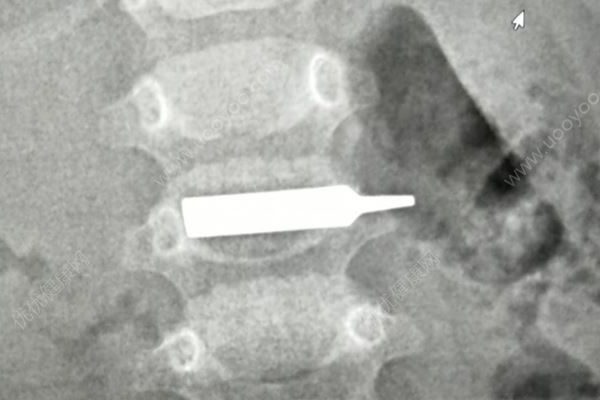

“太惊险了,手术前,这个螺丝刀头一半在胃里,一半已经进入十二指肠,晚一步后果不堪设想。”边鹏介绍,手术还是有很大难度,鹏鹏胃里当时都是食物残渣,手术第一步就是将异物拽回到胃里,这个过程中,异物直接就掉进食物残渣里。“我们先对孩子的胃进行清理,然后才将异物取出。”边鹏说。手术全程2个小时,很顺利,经过测量,发现异物长约3厘米左右,鹏鹏今天可以喝水了,也可以少量的进食些米汤,明后天就可以办理出院了。